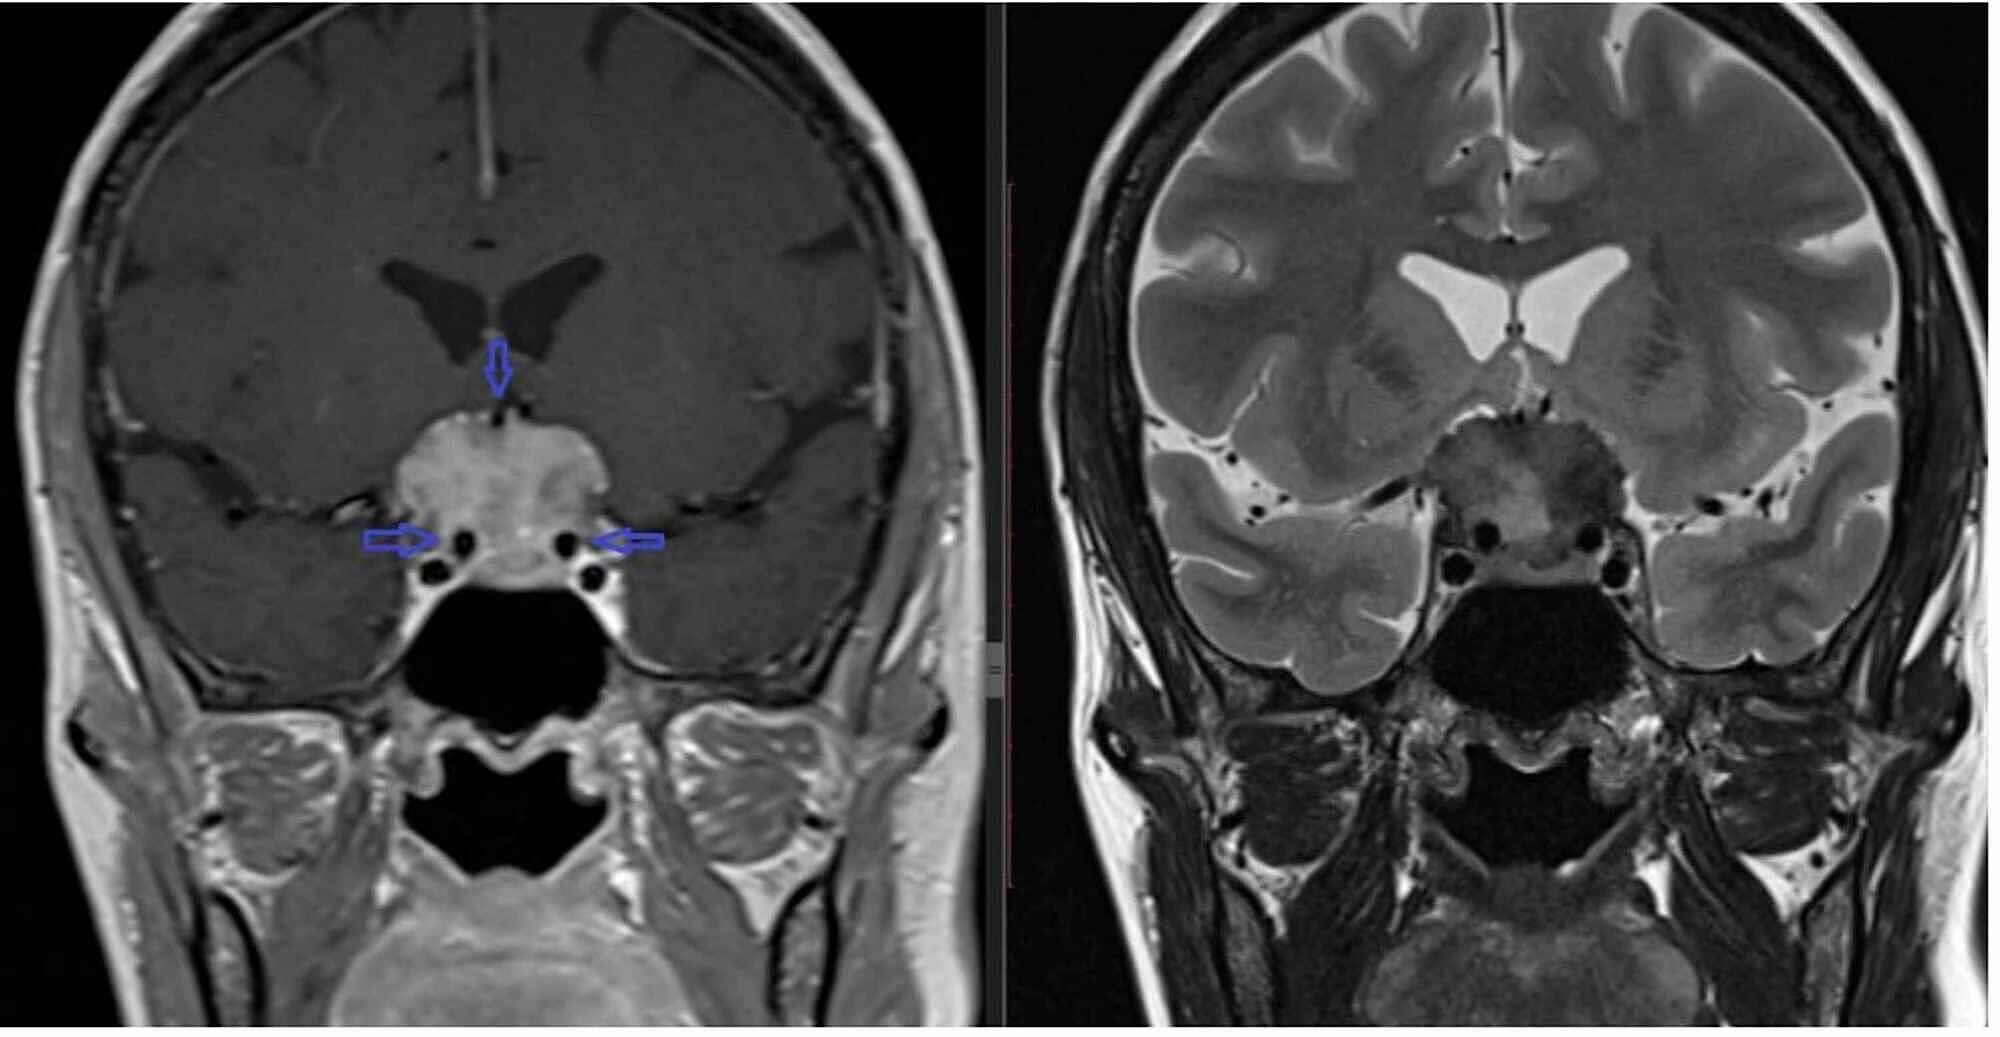

Veterinary Sciences Free FullText First Case of a Cerebrocortical

Veterinary Sciences Free FullText First Case of a Cerebrocortical Will Xray Show Brain Tumor In Dog Since many of the symptoms of brain tumors can appear with other illnesses as well, it's important to determine definitively if your dog has any of. A brain tumor in dogs refers to the uncontrolled growth of cells within the brain or its surrounding structures. Dogs may show more obvious behaviour alterations, appear vacant, irritable, or lethargic. The most common. Will Xray Show Brain Tumor In Dog.